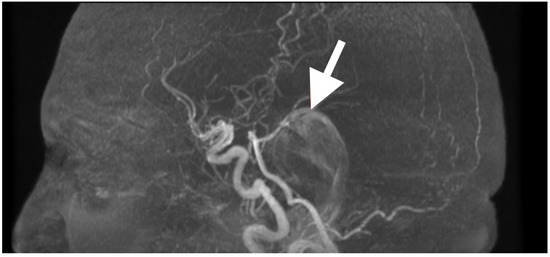

After extubation in the neurosurgical ICU postoperatively, early recovery included trunk stability, improved gaze-holding nystagmus, and less dysmetria. There were no cranial nerve impairments noted, and swallowing remained safe. Postoperative CT (Figure 3) confirmed complete decompression and re-expansion of the fourth ventricle, patency the cerebellomedullary cistern, symmetric cerebellar hemispheres, and patent foramen of Magendie. There was no presence of hemorrhage, infarction or hydrocephalus, and the operative cavity duplicated the original tumor size, underscoring the painstaking extra-axial dissection while maintaining parenchymal margins.

Figure 3. Immediate postoperative non-contrast CT scan demonstrating complete removal of the fourth-ventricular epidermoid tumor and restoration of posterior fossa anatomy. (A) Axial view shows a well-defined postoperative cavity in the midline vermian and fourth-ventricular region, with full re-expansion of the fourth ventricle and reappearance of the cerebellomedullary cistern. The brainstem contour is normalized, and no residual mass effect or obstructive hydrocephalus is present. (B) Coronal reconstruction confirms symmetrical cerebellar hemispheres, midline restoration of the fourth ventricle, and patent foramen of Magendie, with no acute hemorrhage or postoperative edema. The surgical cavity follows the anatomical boundaries of the preoperative lesion, reflecting precise extra-axial microsurgical dissection and preservation of surrounding neural tissue.